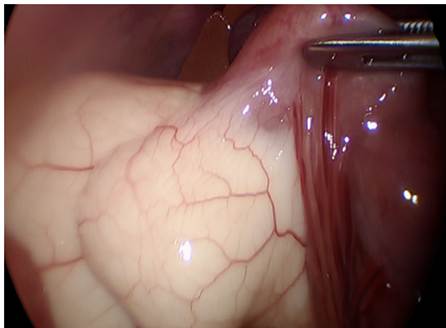

Paciente masculino de dos años con dolor abdominal crónico, tratado como gastroenteritis a repetición, con un examen físico dentro de lo normal. En la ecografía y TC abdominales se detectó una lesión quística septada, localizada en la fosa ilíaca derecha, posterior a la vejiga, de 63x54x52 mm, por lo que fue llevado a laparoscopia, con resección de tres lesiones quísticas de contenido quiloso, localizadas en el mesenterio del yeyuno a 15 cm del ángulo de Treitz (Figura 1). Además, se drenó un líquido peritoneal turbio encontrado en la pelvis y la gotera parietocólica. Después de tres días de tratamiento antibiótico fue dado de alta sin complicaciones. En el control postoperatorio se encontró un paciente asintomático, y el reporte de patología informó un quiste revestido de células planas, compatible con linfangioma.